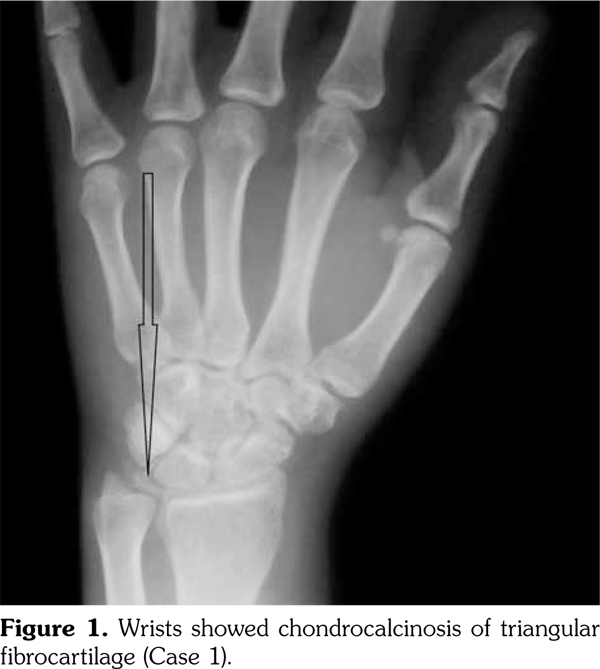

On examination, there was swelling and painful restriction of movement in her right knee. Imaging revealed calcification of cartilage of wrists, knee joints and hip joints although no microscopic confirmation was possible at this stage (Figure 1-4). She was investigated for a possible cause for CC, although investigations to screen for a metabolic cause turned out to be negative with a possibility for hereditary CC.

His hand X-rays showed hook like projections arising from radial aspect of second and third metacarpal heads with scapholunate advanced collapse and indentation of distal radius by the scaphoid bone. It also showed CC of the triangular fibrocartilage (Figure 6).